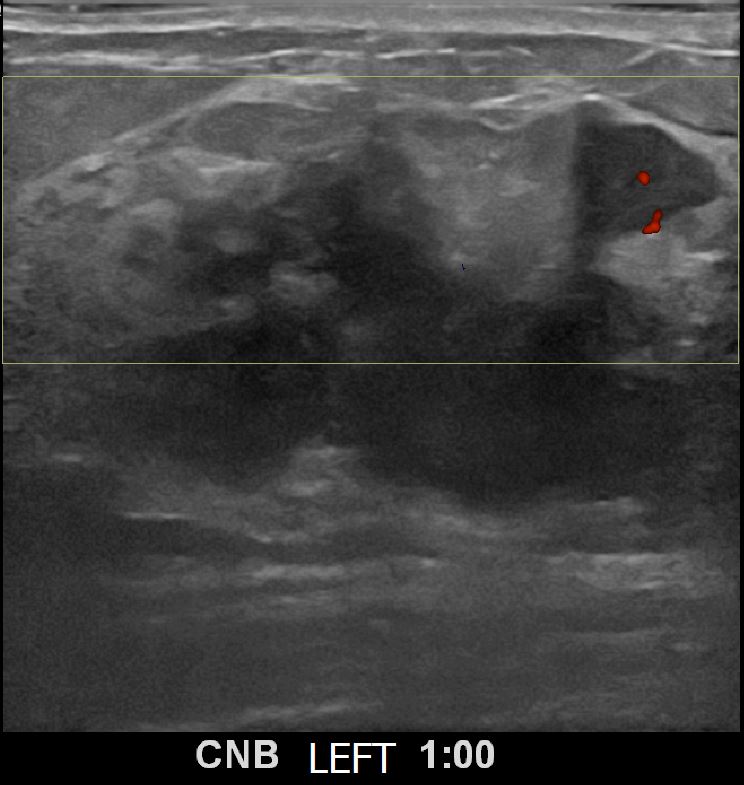

상기환자 좌측유방멍울만져져 내원하신 50대 여성분으로 유방암 의심혹 조직검사 시행 후 유방암 진단되었습니다.